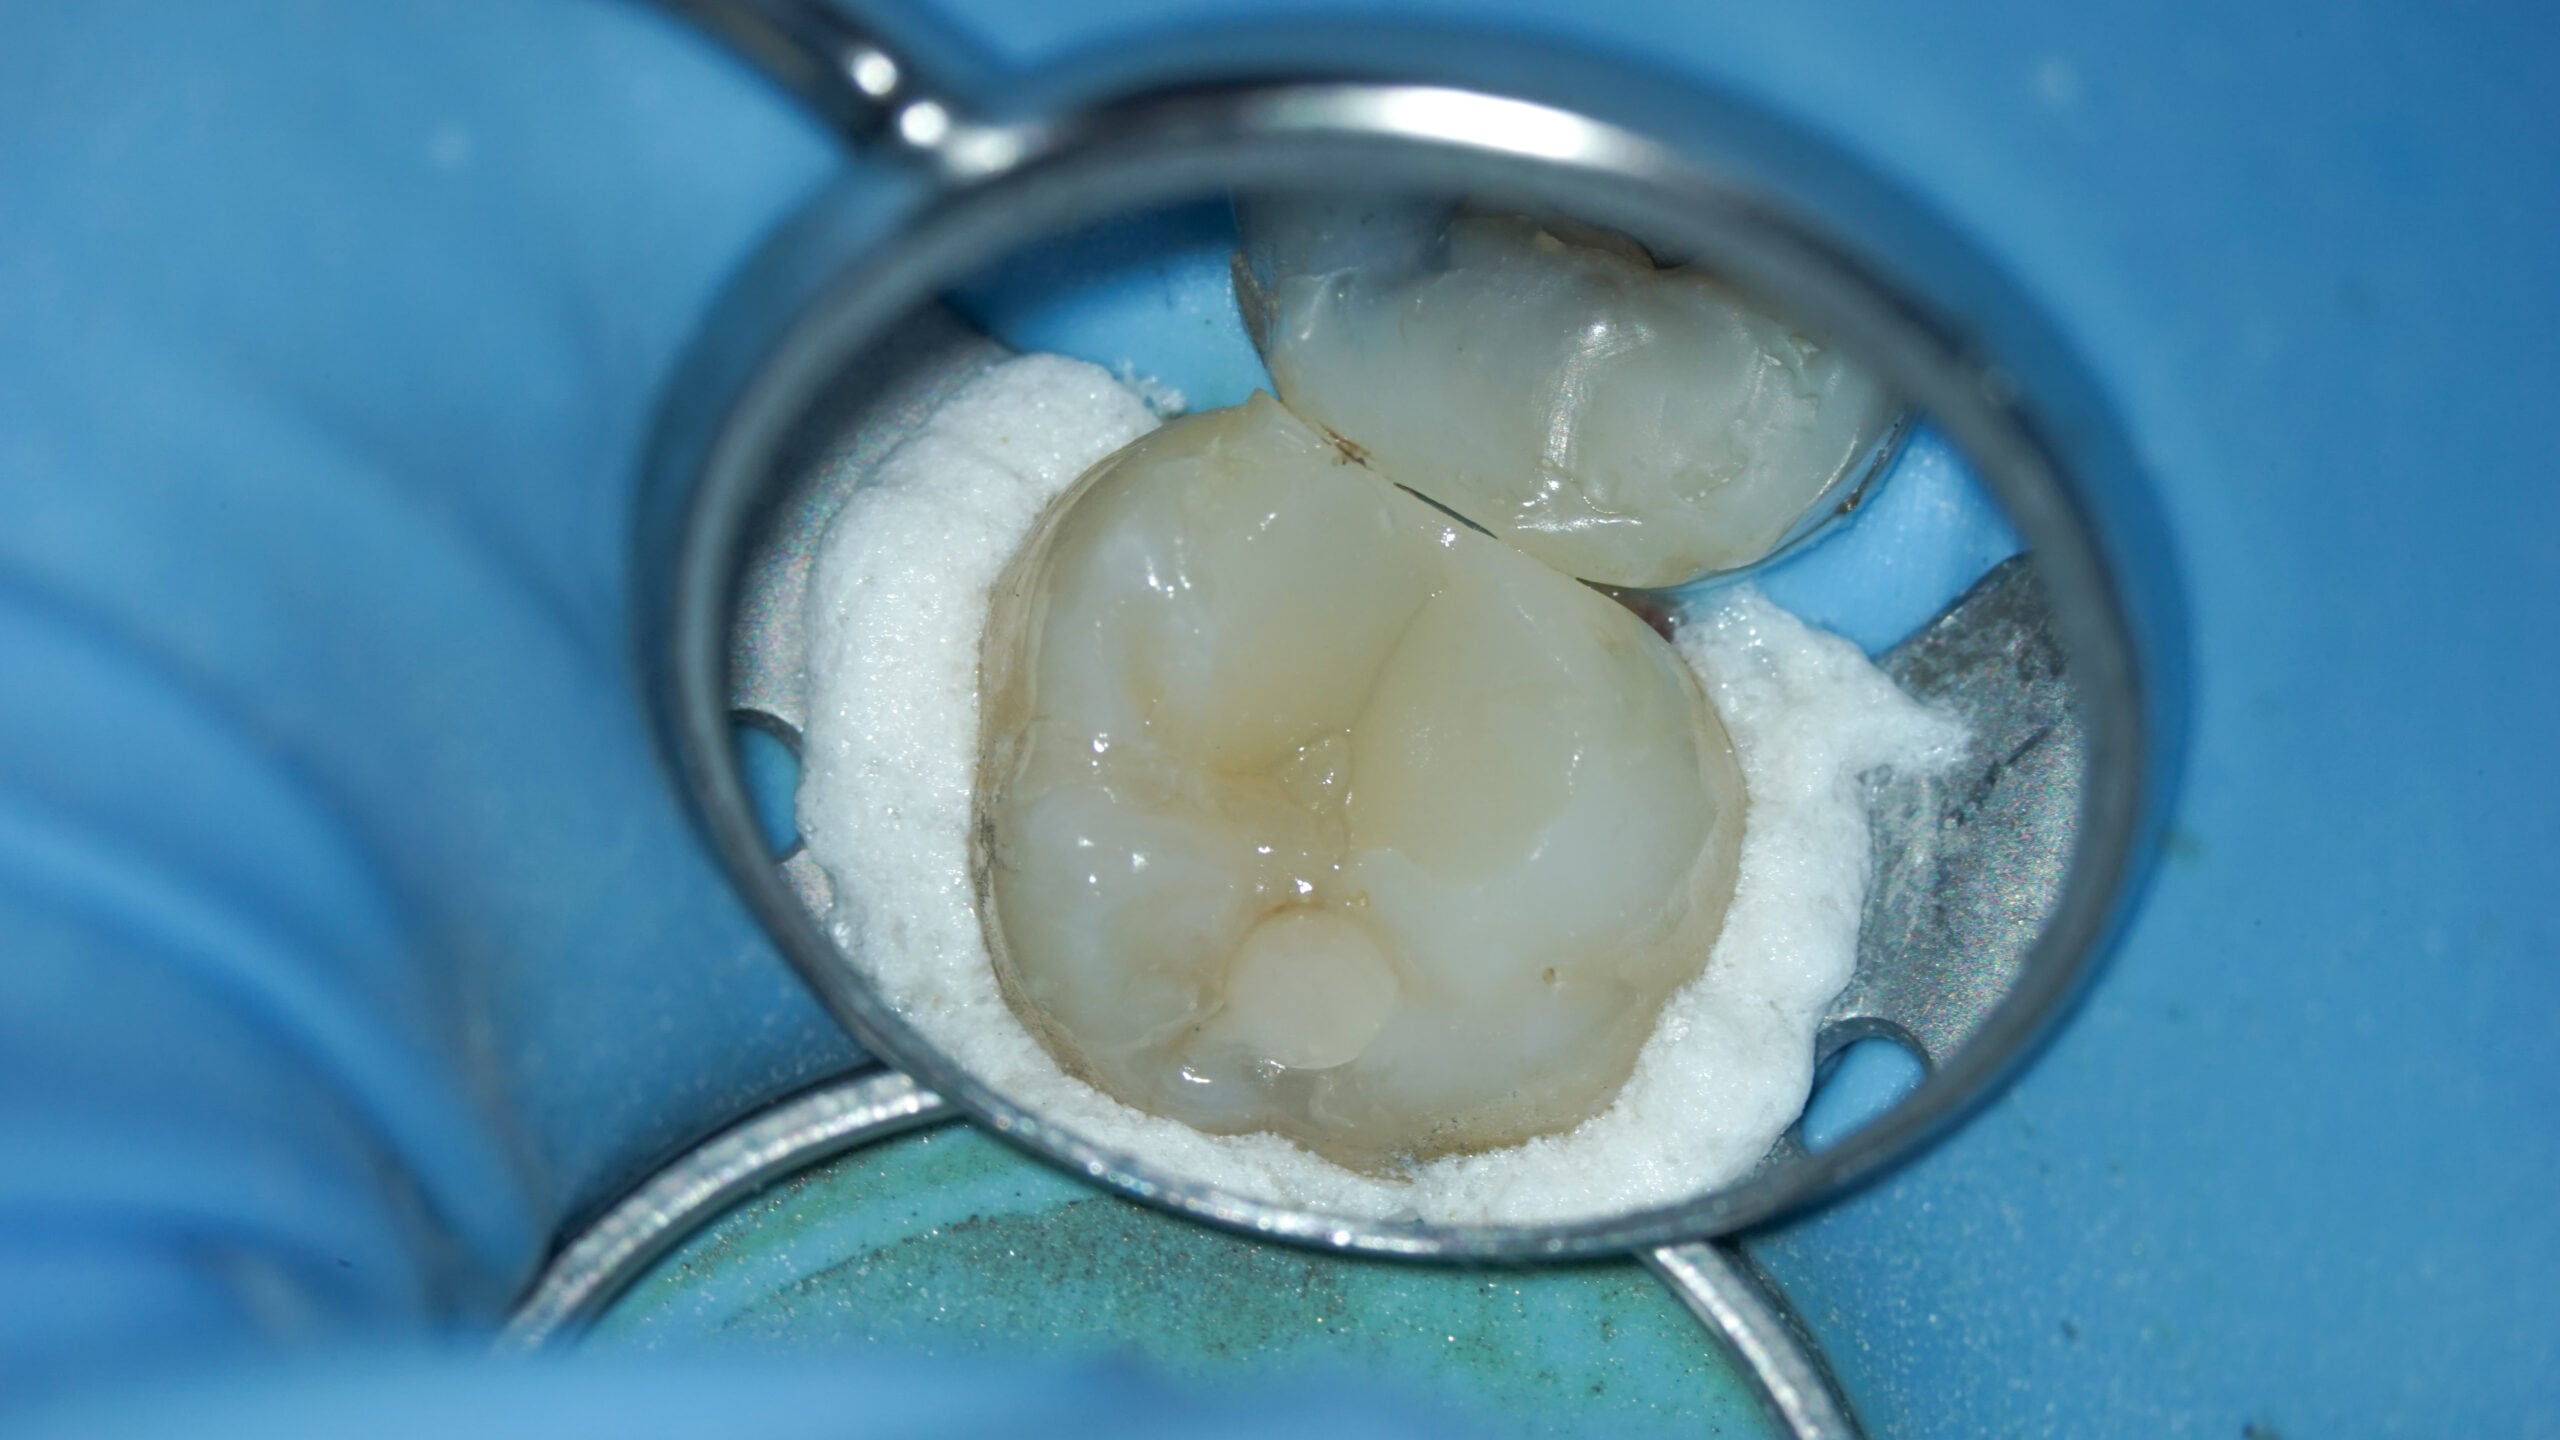

Patient B: Pulpal necrosis and a zirconia crown

In this case, the patient presented with a zirconia crown on the affected tooth and was referred to Dr. Michiels by his general dentist. Zirconia crowns are more challenging to penetrate and can reduce visibility of the pulp chamber, the access cavity, and even the root canals themselves.

Radiographs taken prior to treatment revealed another complicating factor: calcified mesial canals. These are particularly hard to locate once the crown has been opened, requiring extra precision and care during the procedure.